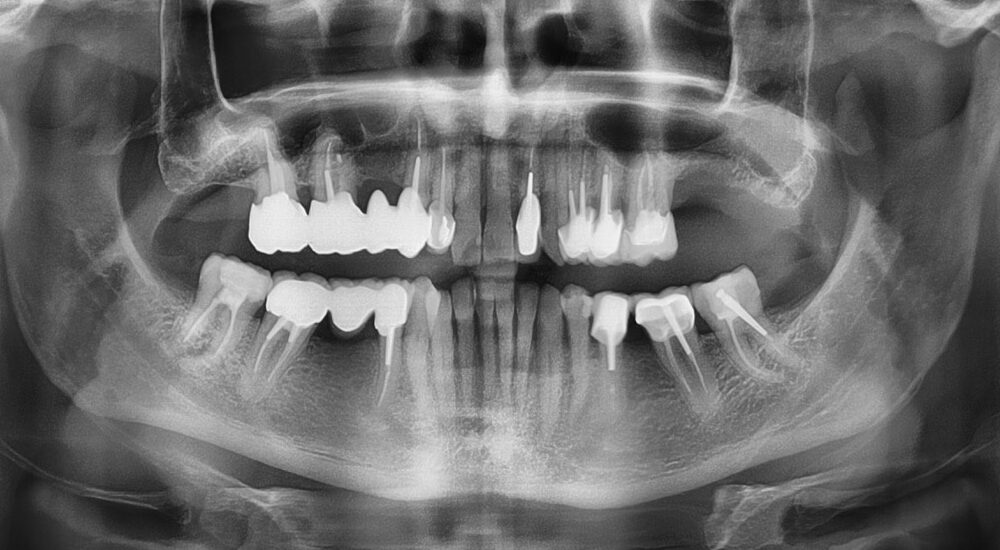

Dans cette master class, le Dr Nicolas Girard met en relief les nombreuses indications du CBCT dans un exercice d’omnipratique.

Les indications du cone beam sont nombreuses et vont augmenter à l'avenir, compte tenu de l'influence de plus en plus marquée du numérique....